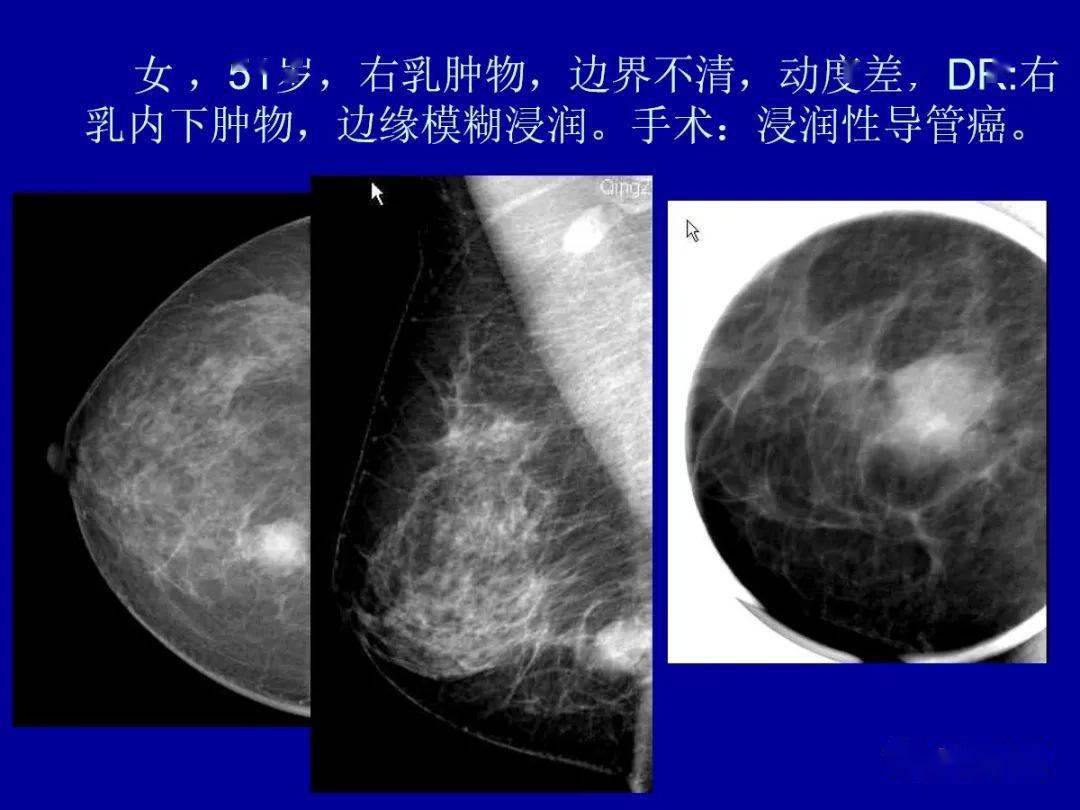

乳腺癌的影像诊断

乳腺疾病影像学诊断讲座(二十四-乳腺癌典型病例随访分享(15)